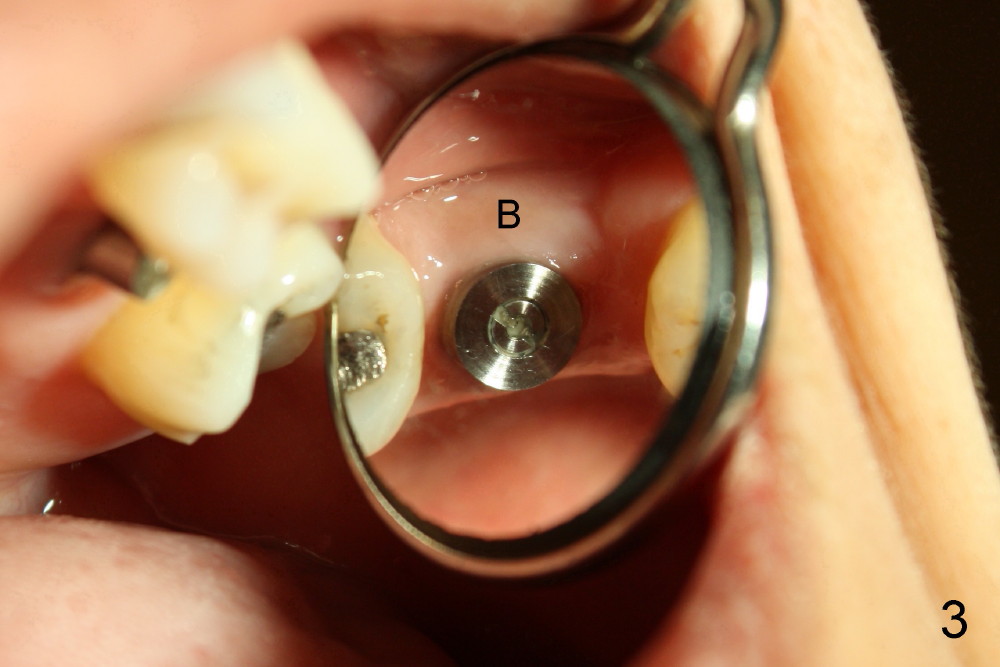

Prior to placement of 6x17 mm soft tissue level implant (Fig.1), the same size of tap is used. When the latter is removed, there is a small defect in the buccal wall of the osteotomy (mainly in the palatal socket) with the intact sinus membrane. There is no intraop or postop nasal hemorrhage. The patient returns for restoration 7 months postop; it appears that there is osteo-integration (Fig.2 with the mesial gap getting smaller (>)). The gingiva is healthy buccal (Fig.3: B) and palatal (Fig.4: P). The mesial gap is closed with formation of dense bone 4 years post cementation (Fig.7). Fig.5 is the preop PA of the patient, which shows that the palatal root (pink dashed line) is above the sinus floor and surrounded by the lamina dura. Fig.6 is a coronal section of the 2nd molar of another patient, which shows that the palatal root is 5-6 mm above the sinus floor. Upper Molar Immediate Implant Follow-Up Xin Wei, DDS, PhD, MS 1st edition 10/13/2013, last revision 05/18/2018